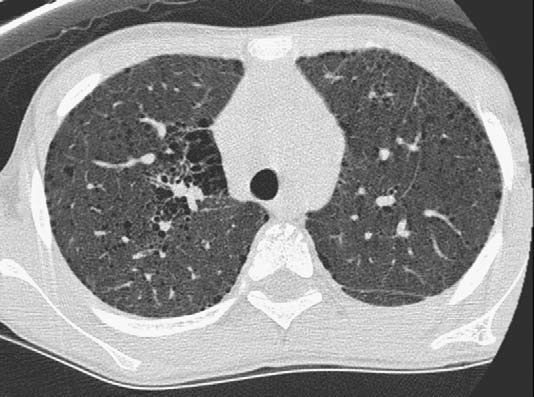

Стандартное рентгенологическое исследование грудной клетки при облитерирующем бронхиолите выявляет гипервентиляцию легких, слабовыраженную диссеминацию по очагово-сетчатому типу, уменьшение легочного объема. КТ легких, являясь более чувствительным методом диагностики, позволяет прижизненно обнаружить характерные признаки облитерирующего бронхиолита: прямые (сужение просвета бронхиол, почковидные разрастания, перибронхиальные утолщения и бронхиолоэктазы) и косвенные (мозаичное снижение прозрачности, сверхпрозрачность пораженных участков бронхиол, признаки «псевдоматового стекла», изменения легочной ткани дистальнее места облитерации).